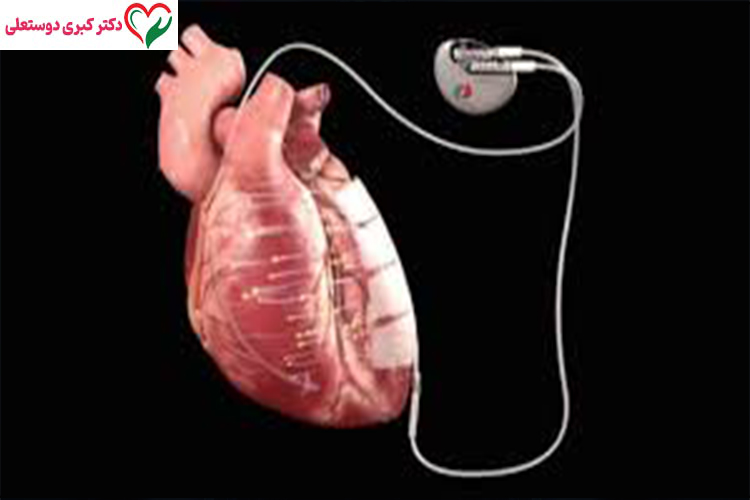

ایمپلنت قلبی یک دستگاه الکترونیکی کوچک است که طی یک جراحی کمتهاجمی در زیر پوست قفسه سینه (معمولاً زیر ترقوه) قرار داده میشود. این دستگاه از طریق سیمهایی به نام لید (Lead) به داخل قلب متصل میشود.

اجزای اصلی ایمپلنت قلبی

یک دستگاه کاشتنی قلب معمولاً شامل:

- ژنراتور (باتری قلب)

- مدار الکترونیکی هوشمند

- لیدها یا سیمهای انتقال سیگنال

است.

ایمپلنت قلبی یک دستگاه الکترونیکی کوچک است که طی یک جراحی کمتهاجمی در زیر پوست قفسه سینه (معمولاً زیر ترقوه) قرار داده میشود. این دستگاه از طریق سیمهایی به نام لید (Lead) به داخل قلب متصل میشود.

اجزای اصلی ایمپلنت قلبی

یک دستگاه کاشتنی قلب معمولاً شامل:

- ژنراتور (باتری قلب)

- مدار الکترونیکی هوشمند

- لیدها یا سیمهای انتقال سیگنال

است.